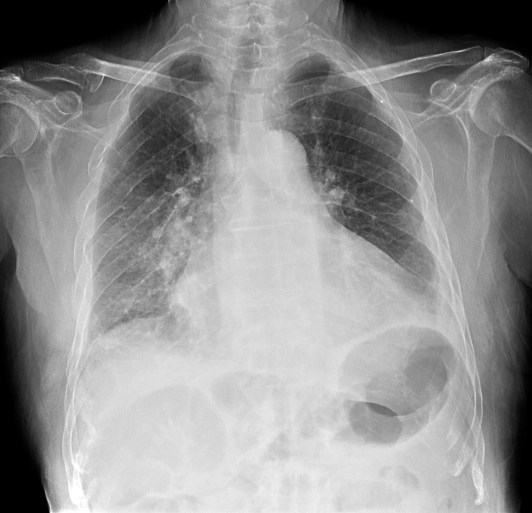

CASO: sospecha de neumonía.

Hallazgos:

- En un principio podríamos decir que existe un aumento de densidad retrocardiaco que podría ser compatible con condensación neumónica a dicho nivel, sin embargo estamos ante una placa poco inspirada, lo cual puede llevarnos a cometer errores diagnósticos.

- Se recomendó volver a realizar la radiografía, observar a continuación:

Ya no se observa el aumento de densidad retrocardiaco, la placa es normal.

INSPIRACIÓN: Una placa bien inspirada es aquella en la que se observar 6-7 arcos costales anteriores o 10-11 arcos costales posteriores. Lo contrario puede producir imágenes falsas de condensaciones o de seudocardiomegalia.